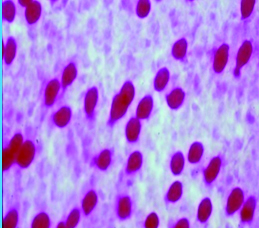

La citología de impresión (Fig. 16) permite identificar los cambios metaplásicos experimentados por la superficie epitelial conjuntival como consecuencia del ojo seco e identificar las características histológicas de las células mucosecretantes y de otras células que conforman a la superficie epitelial conjuntiva.

Figura 16: Citología de impresión

Permite diferenciar cuadros de ojo seco, de alergia, de disfunción de glándula de Meibomio, de toxicidad y realizar un correcto diagnóstico diferencial. Estudios comparativos con biopsia labial de pacientes portadores de Síndrome de Sjögren 22 le dan un gran valor diagnóstico de esa enfermedad.

Es de gran utilidad para diagnosticar disfunciones límbicas.